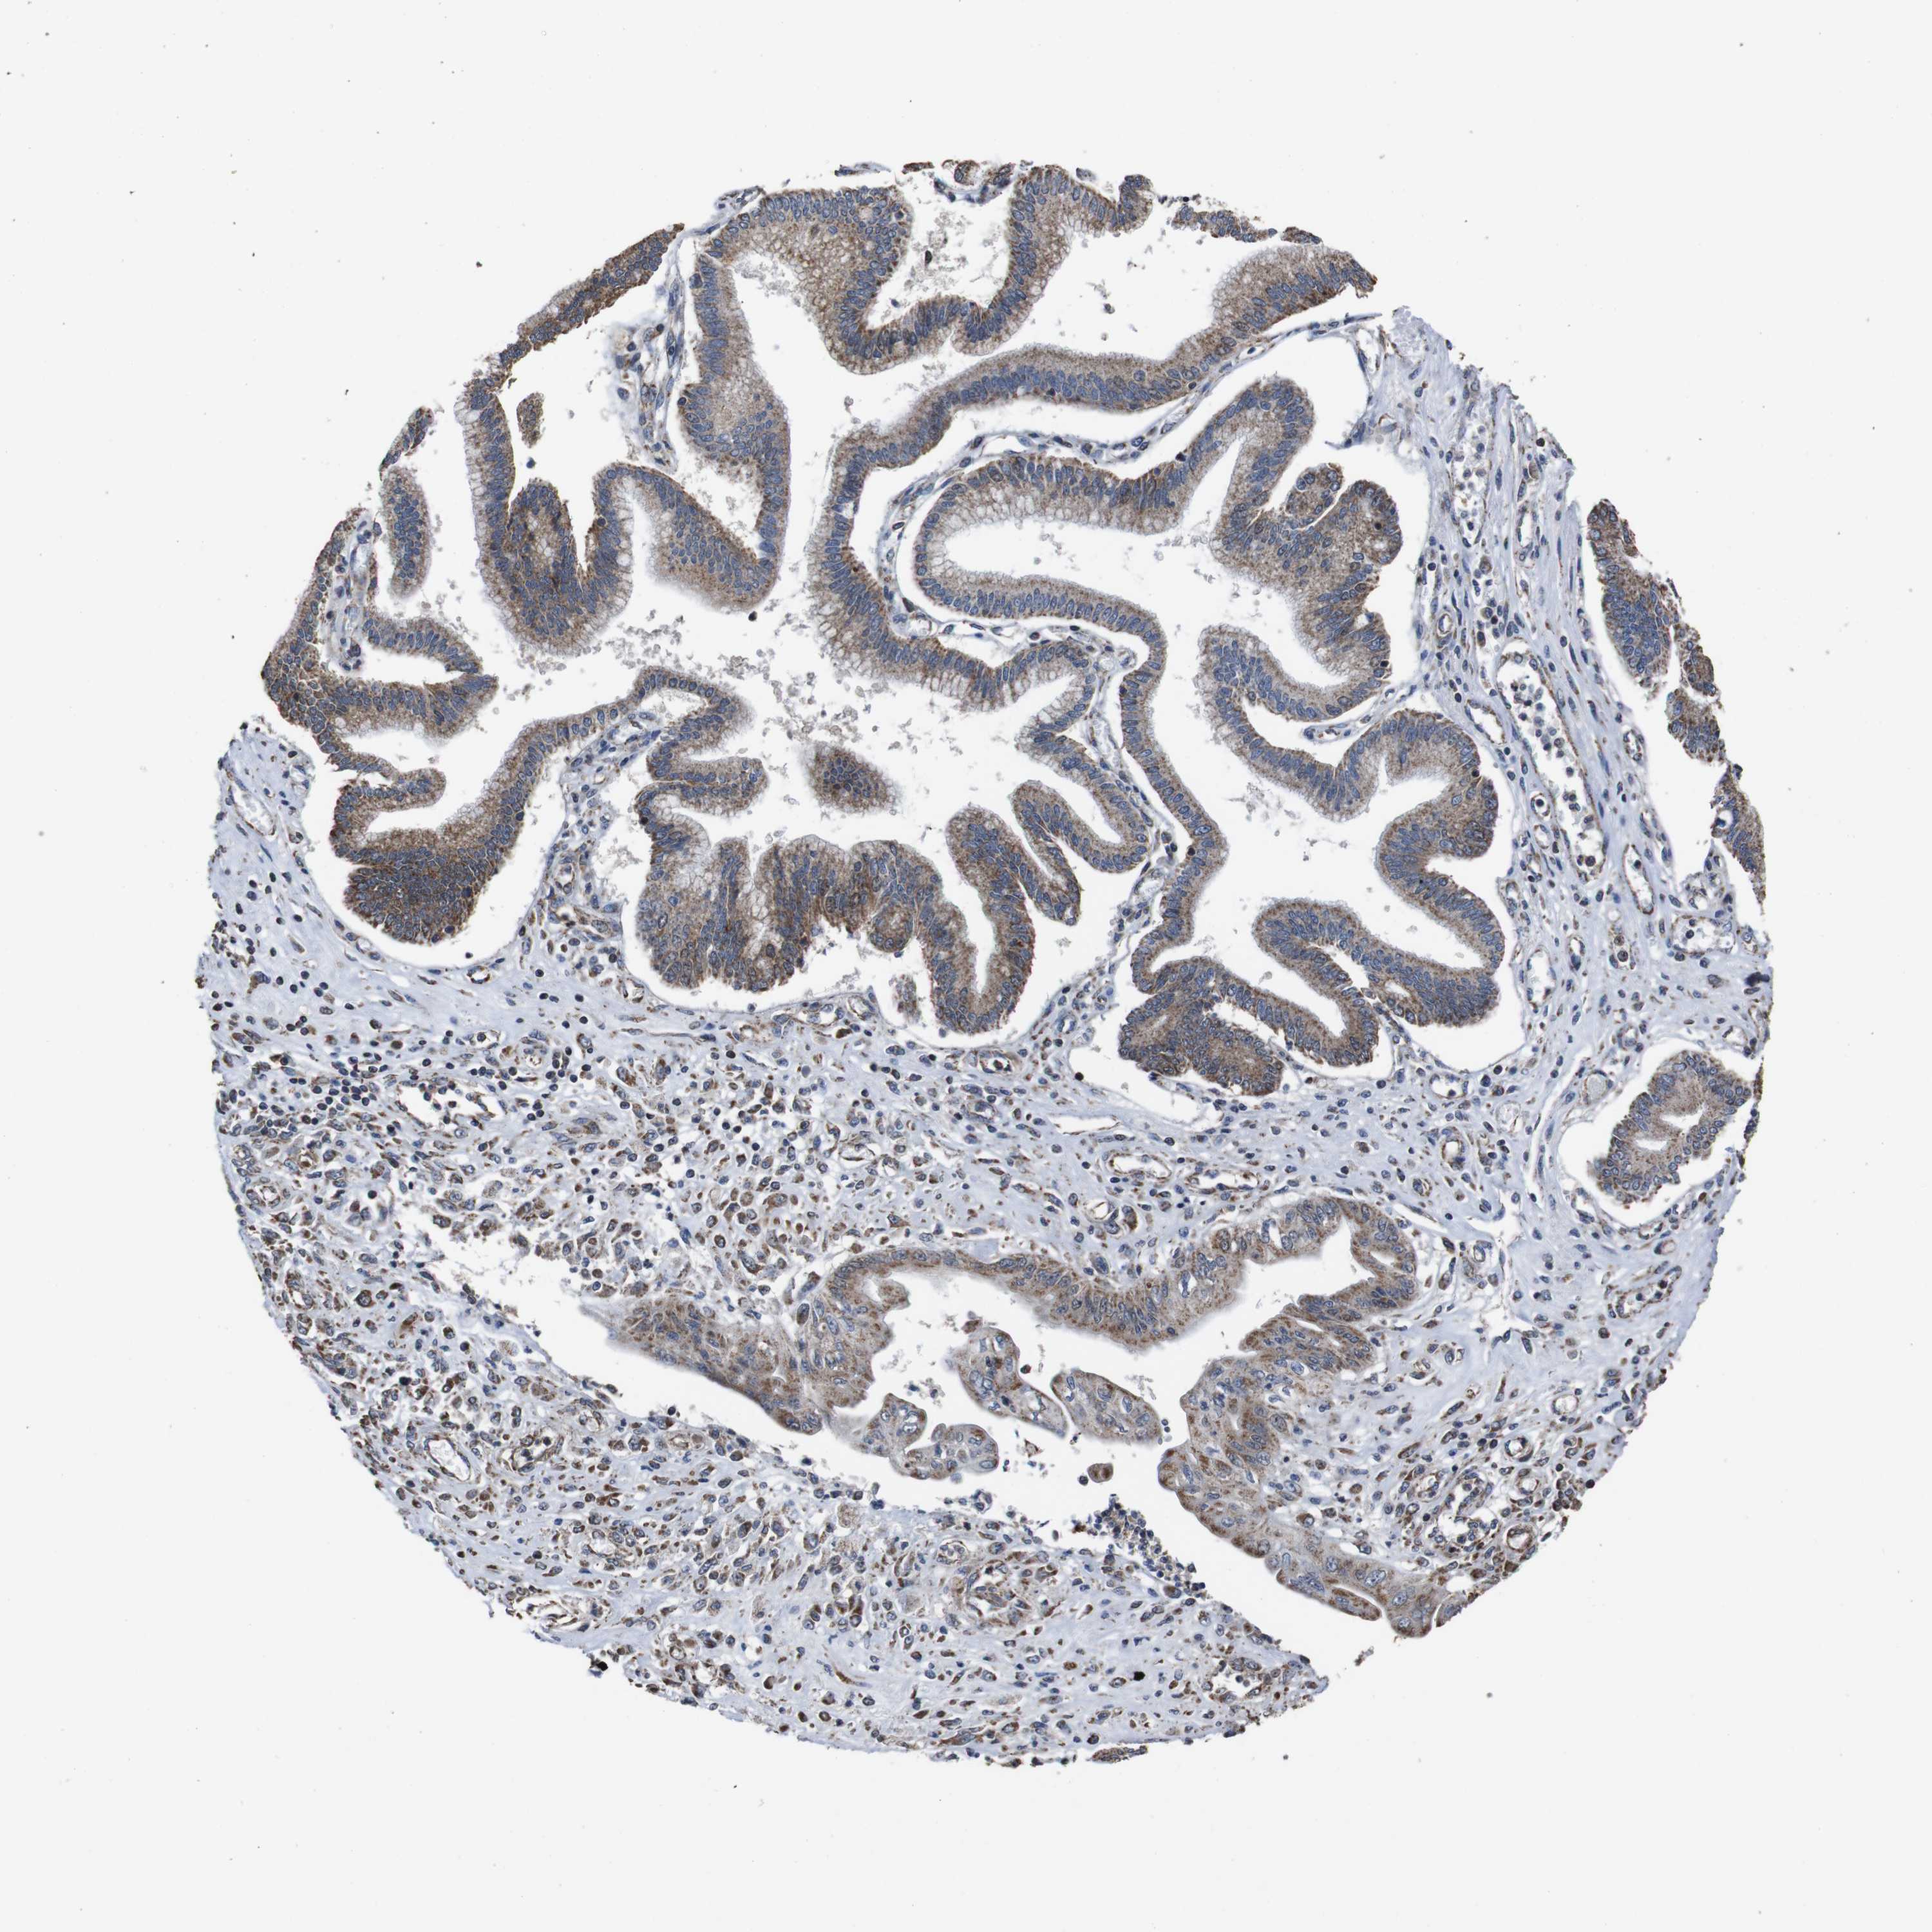

PANCREATIC CANCER - Protein expressioni

A mouse-over function shows sample information and annotation data. Click on an image to view it in a full screen mode. Samples can be filtered based on level of antibody staining by selecting one or several of the following categories: high, medium, low and not detected. The assay and annotation is described here.

Note that samples used for immunohistochemistry by the Human Protein Atlas do not correspond to samples in the TCGA dataset.

Antibody stainingi

Antibody staining in the annotated cell types in the current human tissue is reported as not detected, low, medium, or high, based on conventional immunohistochemistry profiling in selected tissues. This score is based on the combination of the staining intensity and fraction of stained cells.

Each image is clickable and will lead to virtual microscopy that enables deeper exploration of all samples and also displays staining intensity scores, fraction scores and subcellular localization as well as patient and tissue information for each sample.

Antibody HPA011055

Staining

High

Medium

Low

Not detected

Intensity

Strong

Moderate

Weak

Negative

Quantity

>75%

75%-25%

<25%

None

Location

Nuclear

Cytoplasmic/membranous

Cytoplasmic/membranous,nuclear

Adenocarcinoma, NOS